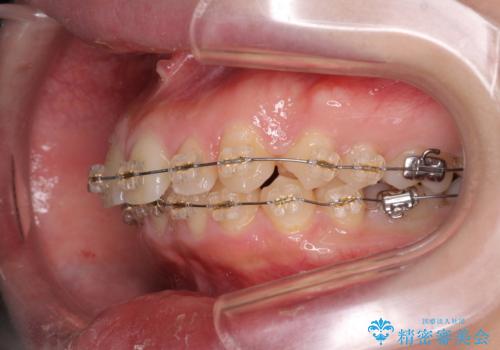

深い噛み合わせ、すきっ歯の改善 ワイヤーを用いたマルチブラケット矯正

- 噛み合わせが深く、前歯が突き出て隙間が出てきたことの改善を希望され矯正治療の相談で当院に初診来院されました。

ワイヤーを用いたマルチブラケット矯正を行うことで深い噛み合わせを改善し、前歯の隙間もなくし審美的な歯列へと治療をおこなっていきます。

深い噛み合わせの改善は前歯の圧下が必要なため、治療期間が長期化することが多いです。